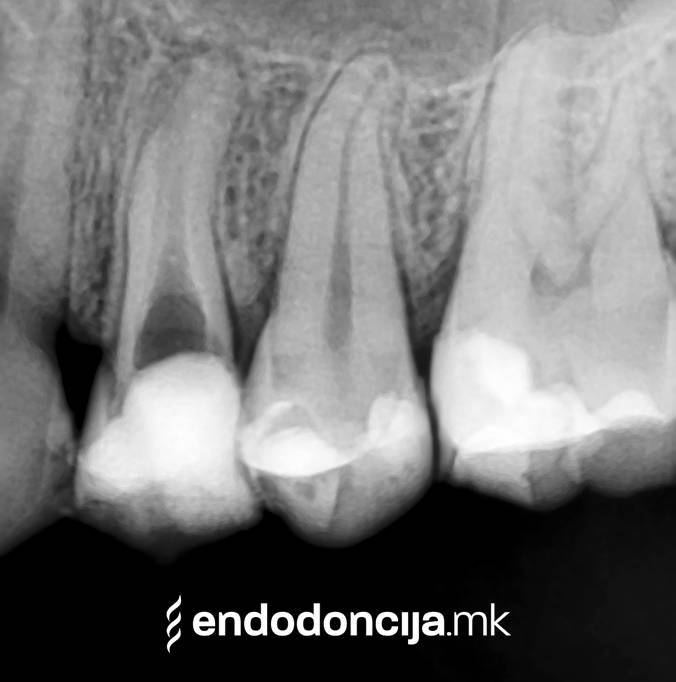

Σε περίπτωση ανανέωσης της θεραπείας του ριζικού καναλιού (αναθεώρηση) παλιά γεμίσματα ρίζας που δεν ήταν επιτυχημένα και ως εκ τούτου ήταν η αιτία φλεγμονών και πόνου, μπορούν να αφαιρεθούν και να ανανεωθούν εξειδικευμένα. Αυτή η θεραπεία εξαλείφει τις φλεγμονές στην περιοχή της ρίζας και καθίσταται δυνατή η πλήρης ανάρρωση.